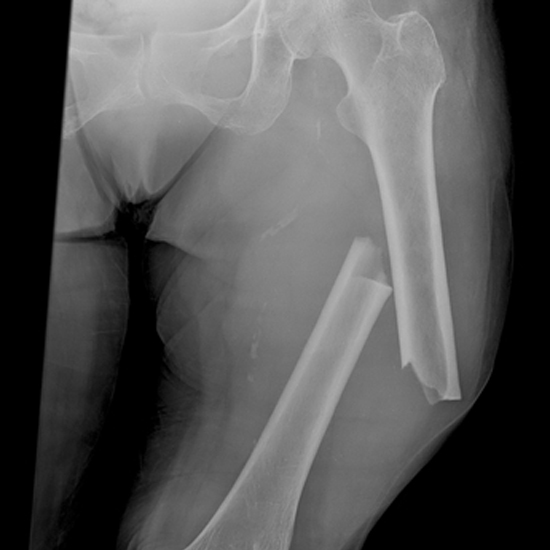

Заклади охорони здоров’я, що розташовані в прифронтових регіонах, а також військові госпіталі та заклади національного рівня отримають 12 нових рентгенівських установок з C-аркою експертного класу. Завдяки такому обладнанню можна проводити хірургічні, травматологічні та інші операції. Про це розповіла заступник міністра охорони здоров’я Марія Карчевич.

«Це друга закупівля обладнання для рентгенологічного обстеження, що дозволяє проводити діагностику пацієнту в момент оперативного втручання. Минулого разу було закуплено для медичних закладів 10 таких установок потужністю 2,3 та 5 кВт. Цього ж разу здійснено закупівлю обладнання експертного класу потужністю 12 кВт. Це особливо важливо для лікування пацієнтів у тяжкому стані, коли точність та швидкість діагностики є критично важливими. Ми швидко ознайомлюємося з потребами медзакладів і як тільки надходять кошти, забезпечуємо їх», — зазначила заступник міністра.

Обладнання придбано коштом пожертв у рамках ініціативи UNITED24. Загалом закуплено 12 рентгенівських установок разом з рентгенопрозорими столами і наборами рентгенозахисного одягу. Міністерством перераховано на рахунок ДП «Медзакупівлі України», яке проводило конкурентні закупівлі, 42,06 млн грн на придбання цих установок.